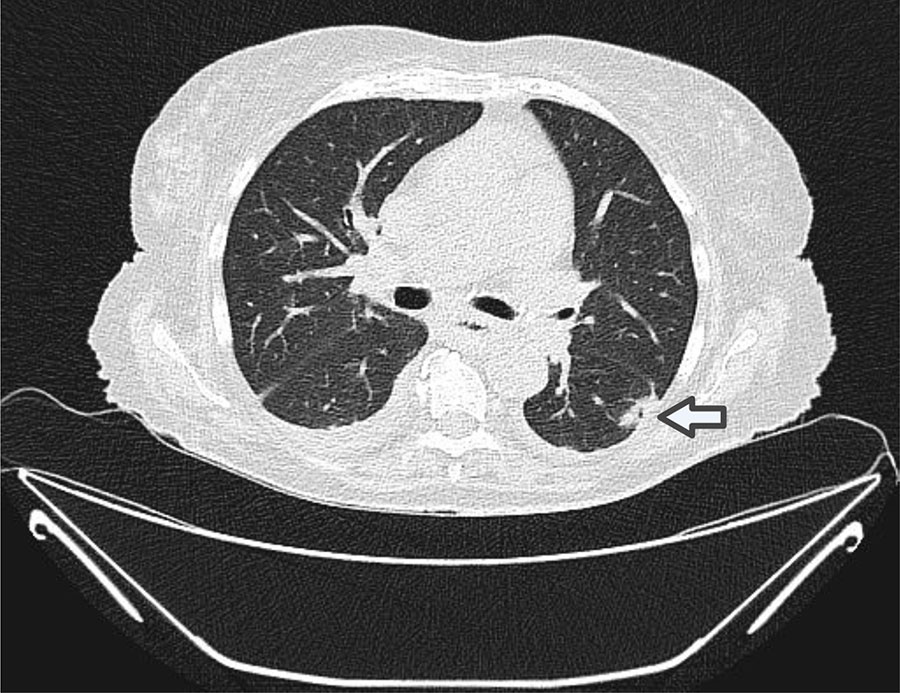

Figure 1. Chest computed tomography scan from an 82-year-old female patient with acute myeloid leukemia in study of Bjerkandera spp. pulmonary infection in immunocompromised hosts, Germany. Image depicts nodular infiltrates and a cavitory lesion (arrow) in the left lower lobe suggestive of fungal pneumonia. We cultured and identified a mold from bronchoalveolar lavage fluid as Bjerkandera spp. by internal transcribed spacer sequencing.